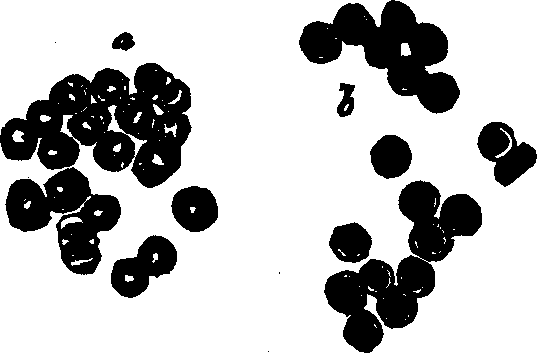

Fig. 38. Red corpuscles of human blood, represented at

a, as they are seen when rather beyond the focus of the

microscope; and at b as they appear when, within the focus.

Magnified 400 diameters.

Fig. 39.

Development of human lymph and chyle-corpuscles into red corpuscles of

blood. A. A lymph, or white blood-corpuscle. B. The same in

process of conversion into a red corpuscle. C. A lymph-corpuscle

with the cell-wall raised up around it by the action of water. D. A

lymph-corpuscle, from which the granules have almost disappeared. E.

A lymph-corpuscle, acquiring color; a single granule, like a nucleus,

remains. F. A red corpuscle fully developed.